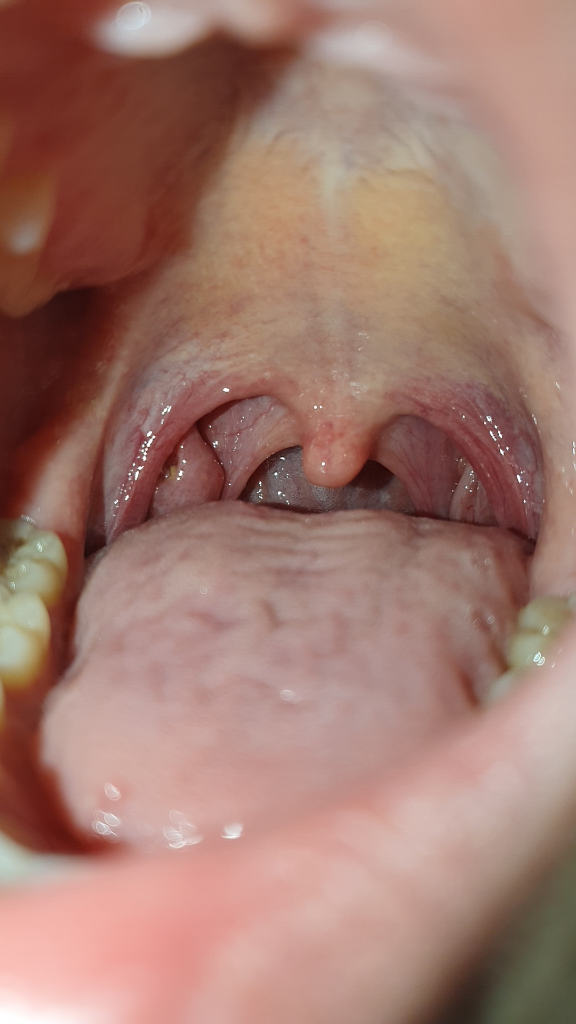

왼쪽에 보면 염증? 같은게 생긴걸 보실수 있는데 무슨 문제가 생긴건지 궁금합니다 인터넷으로 찾아보니까 편도선염이나 역류성 식도염 증상이랑 비슷한데 침을 삼킬 때 이물감을 느끼거나 아무것도 안해도 생선 가시같은 날카로운 무언가가 기도에 낀거같은 이물감이 느껴질 정도로 매우 거슬립니다. 혹시 병원을 갈 정도로 심각한건지 알고싶습니다. 만약에 심각하면 병원에서 어떤 진료를 받아야하는지도 알고싶습니다.

• 1번 째 사진

특별하게 이상은 없어보이며

편도는 다른사람에 비해 큰편입니다. 편도가 크다고 이물감이 발생하지는 않습니다.

아마 주변으로 발적이 있는것으로보아 약간의 염증이 있어 보입니다.

소염제 복용해보세요

• 사진의 소견만으로 정확하게 구분하기는 어렵지만 사진의 소견을 통해서 보았을 때에는 염증이 생겼다기 보다는 편도결석이 있으신 것 같습니다. 관련하여서는 이비인후과적으로 진료 및 검사를 통해서 좀 더 정확하게 감별해 보시고, 편도결석이 맞다면 제거 시술을 받으시는 것을 권고드립니다.